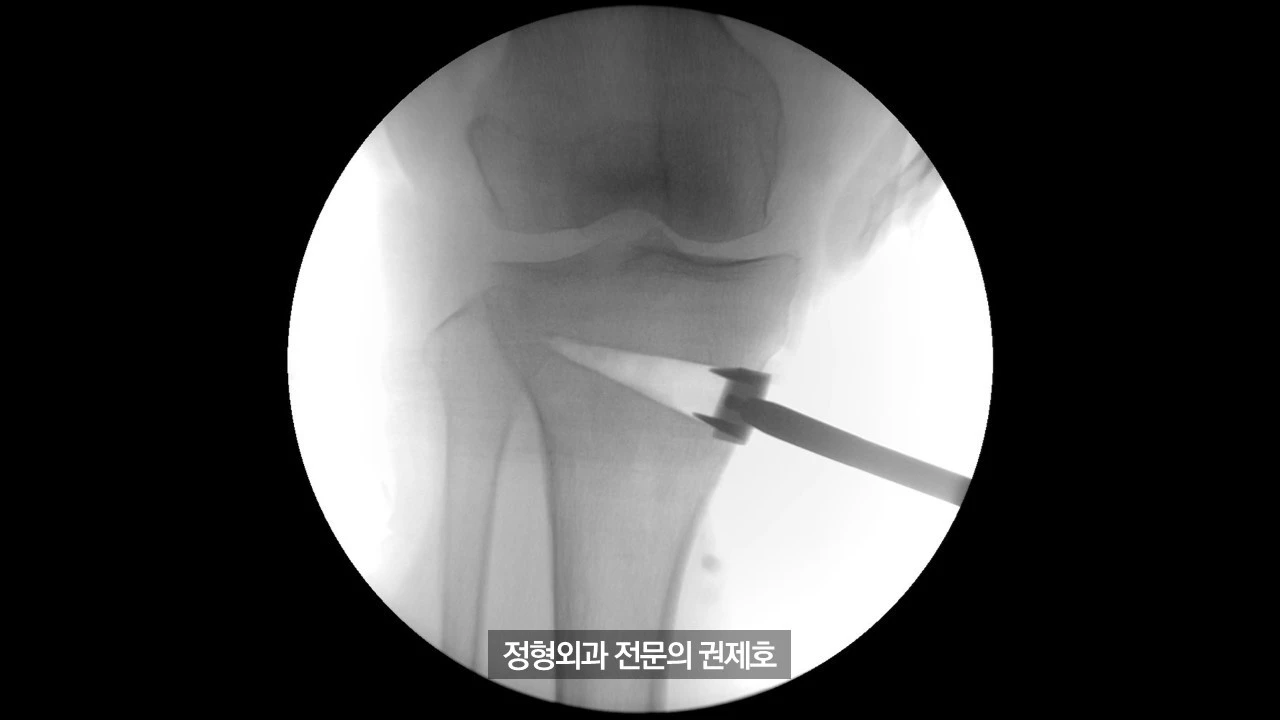

간이 엑스레이 기기를 통해 촬영한 사진이며 (좌측) 가이드 핀을 이용해서 절골할 길을 만드게 되고, (우측) 절골도를 이용하여 천천히 절골을 시행하게 됩니다.

절골도를 이용한 절골이 완료가 되면 이제 절골도 3개를 넣어서 천천히 늘리게 됩니다.